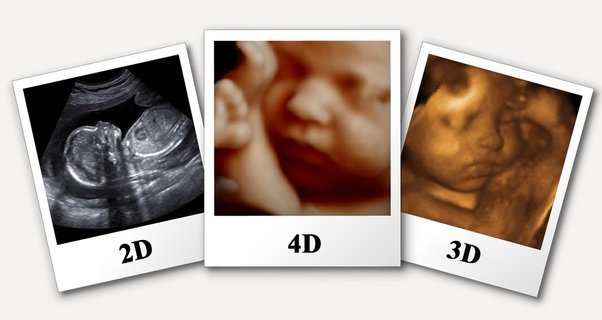

Ultrasound scans including 3D and 4D are more like a real-time photograph of your baby. With 3D scanning, many pictures of the child are taken in 2D and then merged to create a 3D image effect. With 4D scanning, pictures are made in real time and you can see what your child is doing in your womb at the time, such as moving of legs and arms or opening of the eyes.